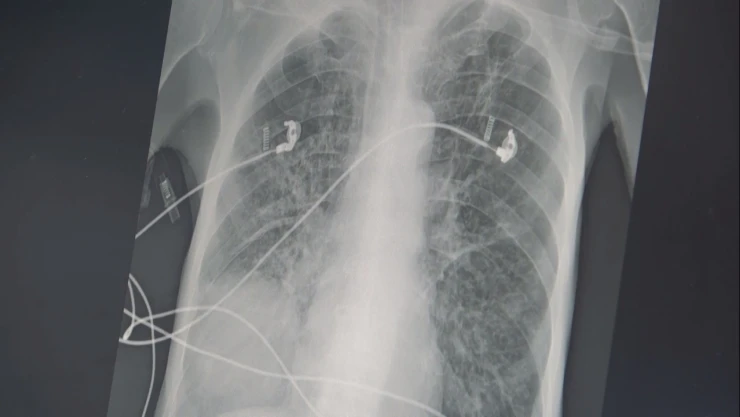

Sigaranın Son 2 Nefesi: Biri KOAH, Diğeri Akciğer Kanseri

Göğüs Hastalıkları Uzm. Prof. Dr. Şevket Özkaya, 'İçtiğiniz sigara 2 ölümcül hastalığın yüzde 90 sebebidir. Biri KOAH, diğeri akciğer kanseridir.' dedi.

Sigara kullanımın zararlarının insanlara anlatmanın artık etkili olmadığını ifade eden Göğüs Hastalıkları Uzm. Prof. Dr. Şevket Özkaya, balon örneği üzerinde sigaranın verdiği zararı anlattı. Sigara kullanımın ortaokul yaşına kadar düştüğünü söyleyen Prof. Dr. Özkaya, "Ülkemizde 20 yaş üstündeki kişilerin en az yarısı sigara bağımlısıdır ve sigaraya başlama yaşı artık ortaokul çağlarına kadar indi. Sigaranın zararları anlatmak artık insanlarımızı etkilemiyor ama içtiğiniz sigara 2 ölümcül hastalığın yüzde 90 sebebidir. Bunlarda biri KOAH, diğeri ise akciğer kanseridir. Eğer yaşınız 40 üzeri ve içtiğiniz sigara paketi ile kullandığınız yılı çarpar, 20 paket/ yıldan daha fazla ise bu iki hastalık ile her an yüzleşebilirsiniz. KOAH teşhisi alan kişilerin büyük çoğunluğu halen sigara içen veya çok uzun süre sigara içmiş ve bırakmış kişilerdir. Hastalık sinsi ilerlediği için ve sigara bağımlıları öksürük, balgam çıkarma gibi şikâyetleri önemsemedikleri için KOAH teşhisi konduğu zaman hastalar akciğer kapasitelerinin önemli bir kısmını kaybetmiş olmaktadırlar" diye konuştu.

Akciğer keseciklerinin tıpkı bir balon gibi olduğuna dikkat çeken Özkaya, "Temiz havayı nefes olarak bu keseciklere aldığınızda şişer ve hava ile dolunca elastik yapısından dolayı içerdeki kirli havayı da tıpkı balonun sönmesi gibi dışarı atar. Bu mekanizma hayat kurtarıcıdır. Ancak sigara içerseniz, kesecik duvarlarınızdaki elastik doku harap olur ve esneme yeteneğini kaybederek tıpkı bu naylon poşet gibi olur ve nefes alırsınız ama balonun elastik yapısı olmadığı için kirli havayı dışarı atamazsınız ve içerde kirli hava kalır. Siz yeni bir temiz havayı nefesle almak istediğinizde keseciklerde temiz havanın gireceği yer kalmayacak ve nefes alamama yani nefes darlığı başlayacak" şeklinde konuştu.

Kişilerin uzun yaşama imkânı da olsa her hücrenin kanserden öleceğini belirten Özkaya, "Sigaranın diğer ölümcül sebebi ise akciğer kanseridir. Biz şunu biliyoruz ki, yaşayan her sağlıklı hücrenin sonu kanser. Eğer diğer hastalıklar, kazalar ve erken ölümler olmasa ve uzun yaşama imkânı olsa her hücre kanserden ölecek. Eğer sigara kullanıyor veya kanserojen maddelere maruz kalıyorsanız, bu kansere yakalanma yaşınızı düşüren bir faktör. Örneğin; 150 veya 170 yaşında akciğer kanseri olacak bir kişi, sigara içtiği için bu yaş 100'e düşüyor. Eğer ailede kanser öyküsü varsa bu yaş daha da düşüyor. Ve 45 yaşından sonra her an kanser gelişmesi ile karşı karşıya kalınıyor. Sigara içmeye hiç başlamayarak bu iki ölümcül nefesten kurtulabilir ya da bırakarak bu iki ölümcül hastalık riskinizi azaltabilirsiniz" şeklinde konuştu.